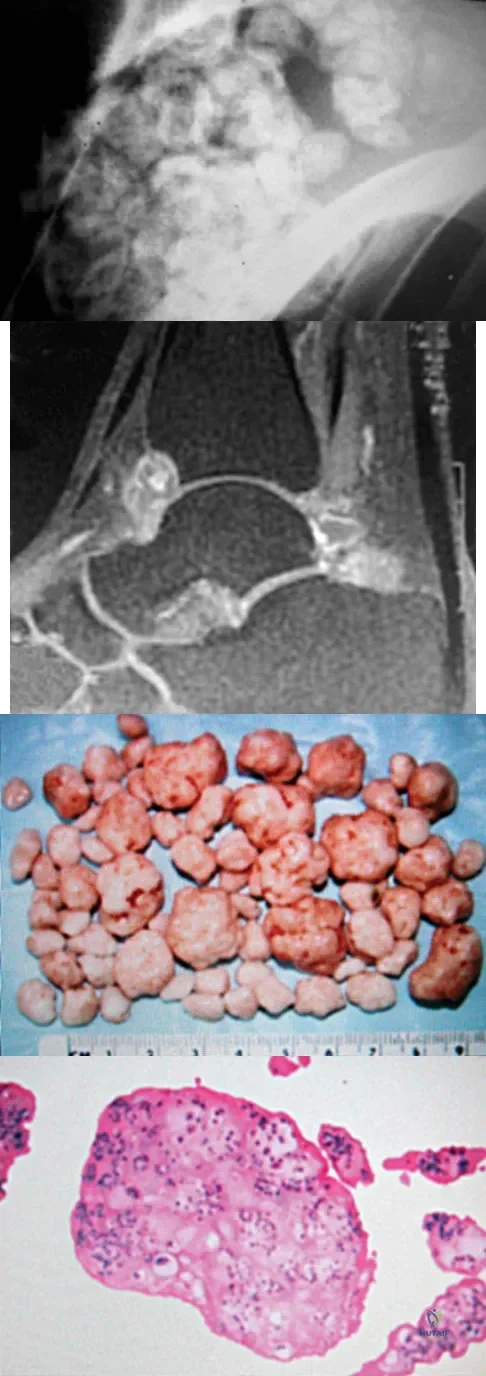

Question 82

A 40-year-old man has a painful mass on his anterior ankle joint with limited range of motion. A radiograph, MRI scan, a gross specimen, and a hematoxylin/eosin biopsy specimen are shown in Figures 5a through 5d. What is the most likely diagnosis?

Explanation